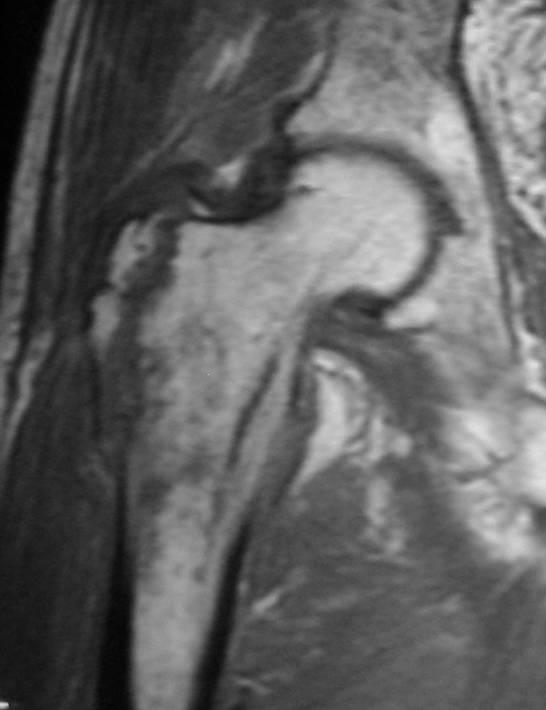

Radiography of the hip demonstrated avulsion of the lesser trochanter and fracture of the greater trochanter with no apparent intertrochanteric extension (Fig. 1). The fracture condition was well revealed by the CT scan (Fig. 2). MRI showed no typical abnormality at the intertrochanteric lesion (Fig. 3). Laboratory data including full blood cell count were normal. NTX/CR was normal. DEXA scan of vertebral bones showed a bone density 0.925 g/cm2, which is 88% of the means Japanese young adults.

Fig. 3 MRI image showing no intertrochanteric fracture

In our case, there was no apparent metastatic or primary tumor around the proximal femur in CT and MRI. During the follow-up no cancer was found. It is suggested that these fractures happened as follows. First, the lesser trochanter fracture occurred as an avulsion fracture when the patient tried not to fall down, then the greater trochanter fracture occurred by a direct blow. It is considered that conservative therapy should be the first choice for isolated greater and lesser trochanteric fractures. It is said that there exists a risk of misdiagnosis of intertrochanteric fracture around these fractures 3), so MRI and CT scans are very important to avoid to rule out any underlying intertrochanteric lesions.